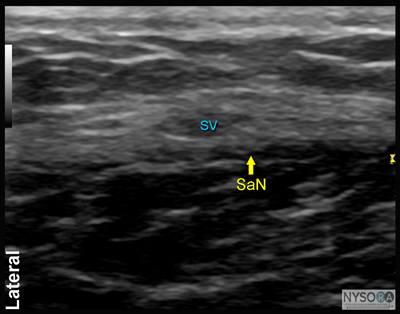

Figure 3: (A) Ultrasound transducer and needle insertion technique to block the saphenous nerve (SaN) at the levelof the tibial tuberosity. (B) Cross-sectional anatomy of the SaN at the level of the tibial tuberosity. (C) Ultrasound image of the saphenous nerve (SaN) at the level below the knee. SaN is seen in the immediate vicinity of the saphenous vein (SV). Transducer should be applied lightly to avoid compression of the saphenous vein (SV) because the vein serves as an important landmark for technique.